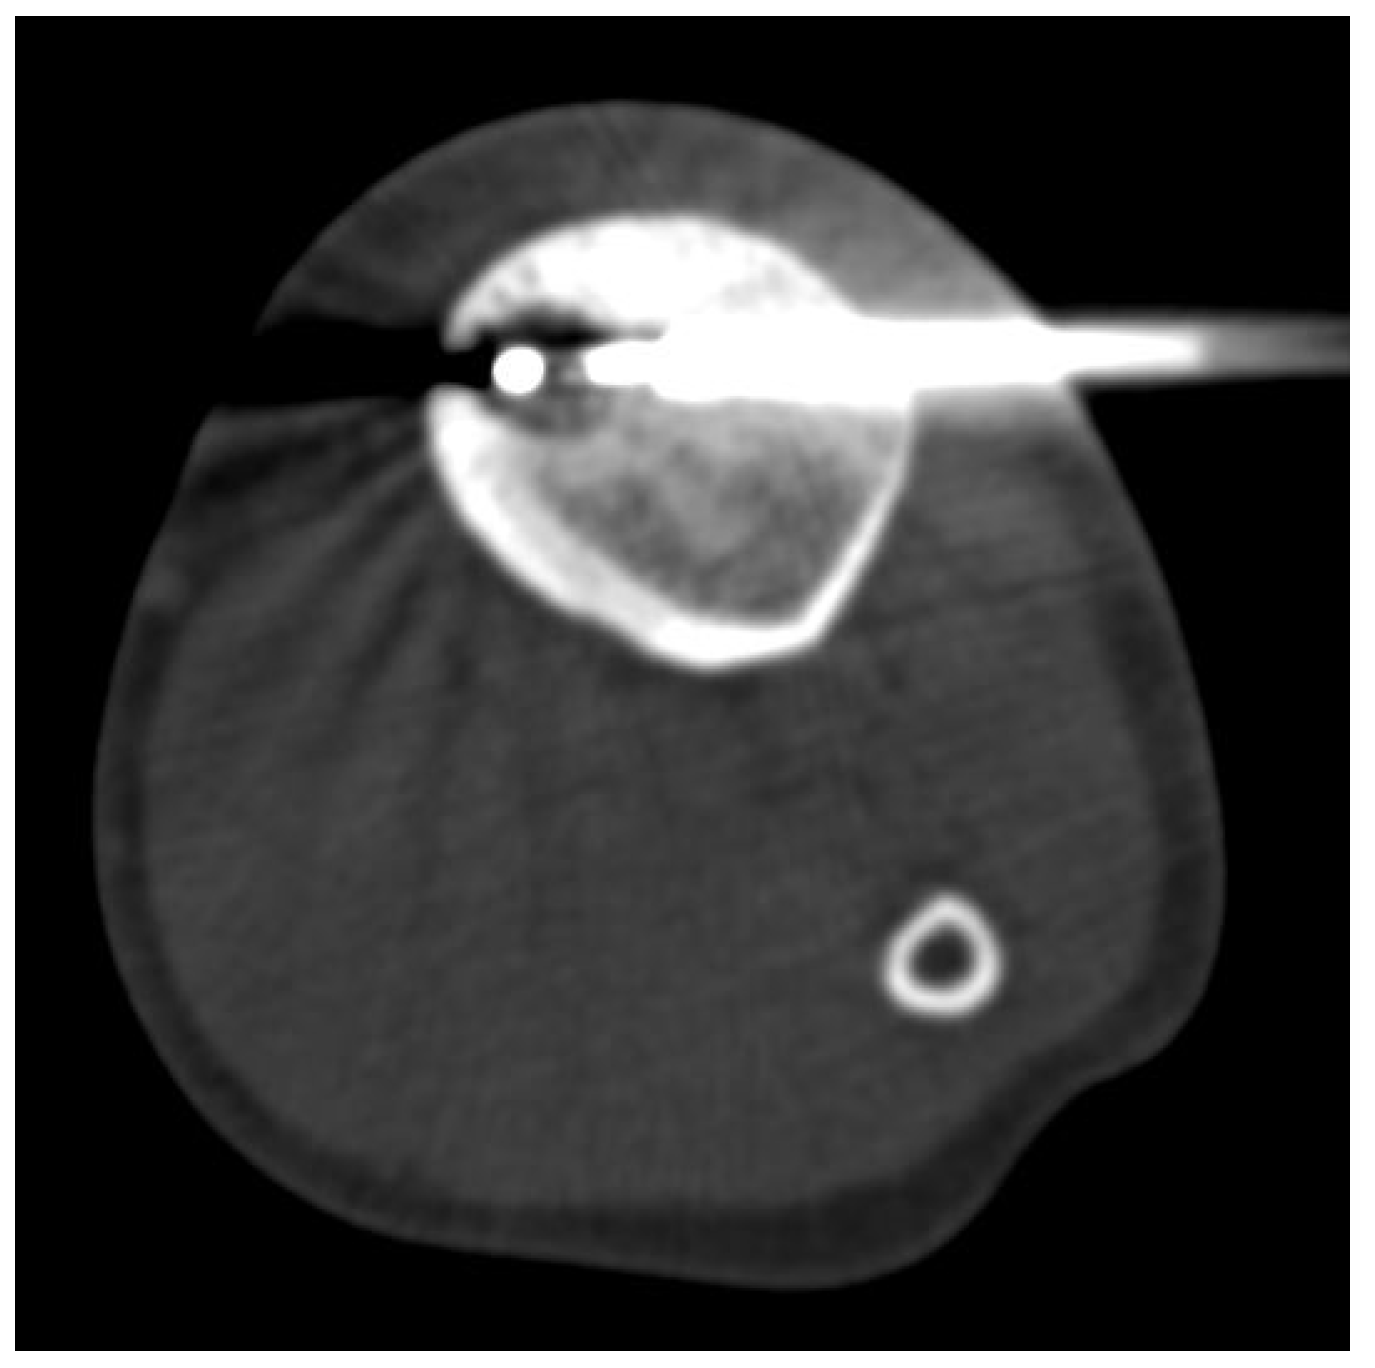

2.2. Procedure